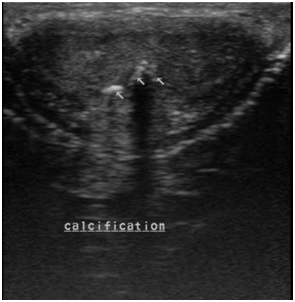

A 48year old male patient , a known diabetic presented with a palpable hard nodular lesion in the middle third of penis since 6months. Local USG of penis showed linear echoreflective calcified plaque in intercorporeal septum extending along the ventral aspect of bilateral corpora cavernosa causing posterior acoustic shadowing (Figure 1A & Figure 1B). A diagnosis of Peyronie’s disease was made. Plain radiograph of penis done with soft tissue exposure confirmed calcification (Figure 2).

Figure 1A Ultrasound mid penile shaft tranverse section shows echoreflective calcified plaques in intercorporeal septum with extension along ventral aspect of bilateral corpus cavernosa (right >left).